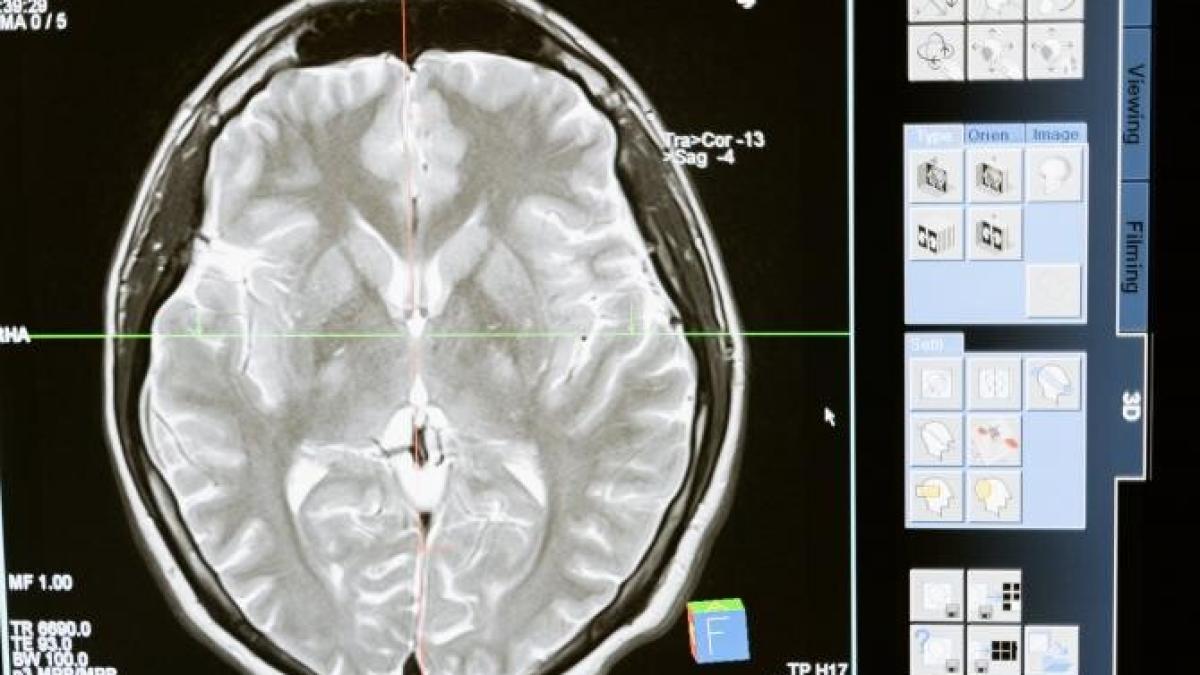

Un pacient ce a suferit o operație asupra vaselor creierului poate pleca din spital la 48 de ore de la intervenție.

Intervențiile minim invazive din sfera neuro-radiologiei pot avea numeroase beneficii fizice, pe lângă cele care țin de rezolvarea unor afecțiuni are pot pune viața în pericol. Timpul de refacere poate fi minim, conform medicului Cristian Mihalea.

„Pot să vă dau 2 exemple avute de curând. O pacientă tratată luni pleacă miercuri acasă sau o pacientă tratată marți pleacă joi dimineața acasă. Reinserția în câmpul muncii, în familie, în ce vreți dumneavoastră este undeva la 48 de ore, cu condiția ca operația să meargă bine. În mâinile mele, pentru că nu pot vorbi despre generalități, în centrul unde noi performăm rata de succes a intervențiilor este de 99%.

N-am văzut un pacient decedând pe masa angiografului în 10 ani de zile de când lucrez. Am văzut pacient decedând la o zi, două, pentru că aveau un anevrism gigant de 3 centimetri sau 2 centimetri, adică vorbim de cazuri extreme. Un anevrism normal, banal, între 8 sau 12 milimetri, se tratează relativ rapid, într-o oră jumătate, două, se externează, pleacă din spital pe picioarele proprii în proporții de 99% după 48 de ore”, a relatat medicul Cristian Mihalea.

Operația decurge sub anestezia generală a pacientului și este nevoie de o perioadă minimă de 24 de ore în spital, pentru a depăși toate efectele pe care anestezia le poate avea asupra unei persoane. De asemenea, evoluția operației trebuie urmărită pentru a elimina orice risc care ar putea surveni.